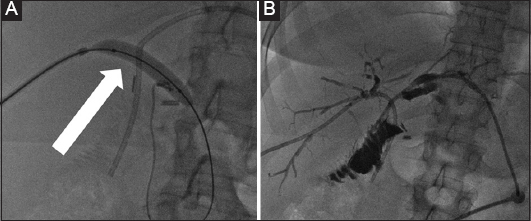

Figure 2 A 45-year-old female patient who developed benign biliary stenosis post laparoscopic cholecystectomy, with presence of stones. (A) Bilateral biliary drainage and dilation of the stenotic anastomosis with a high-pressure balloon (arrow). (B) Long-term drains with discoid end were left in situ for several months and the patient returned every 3 weeks for sequential dilation